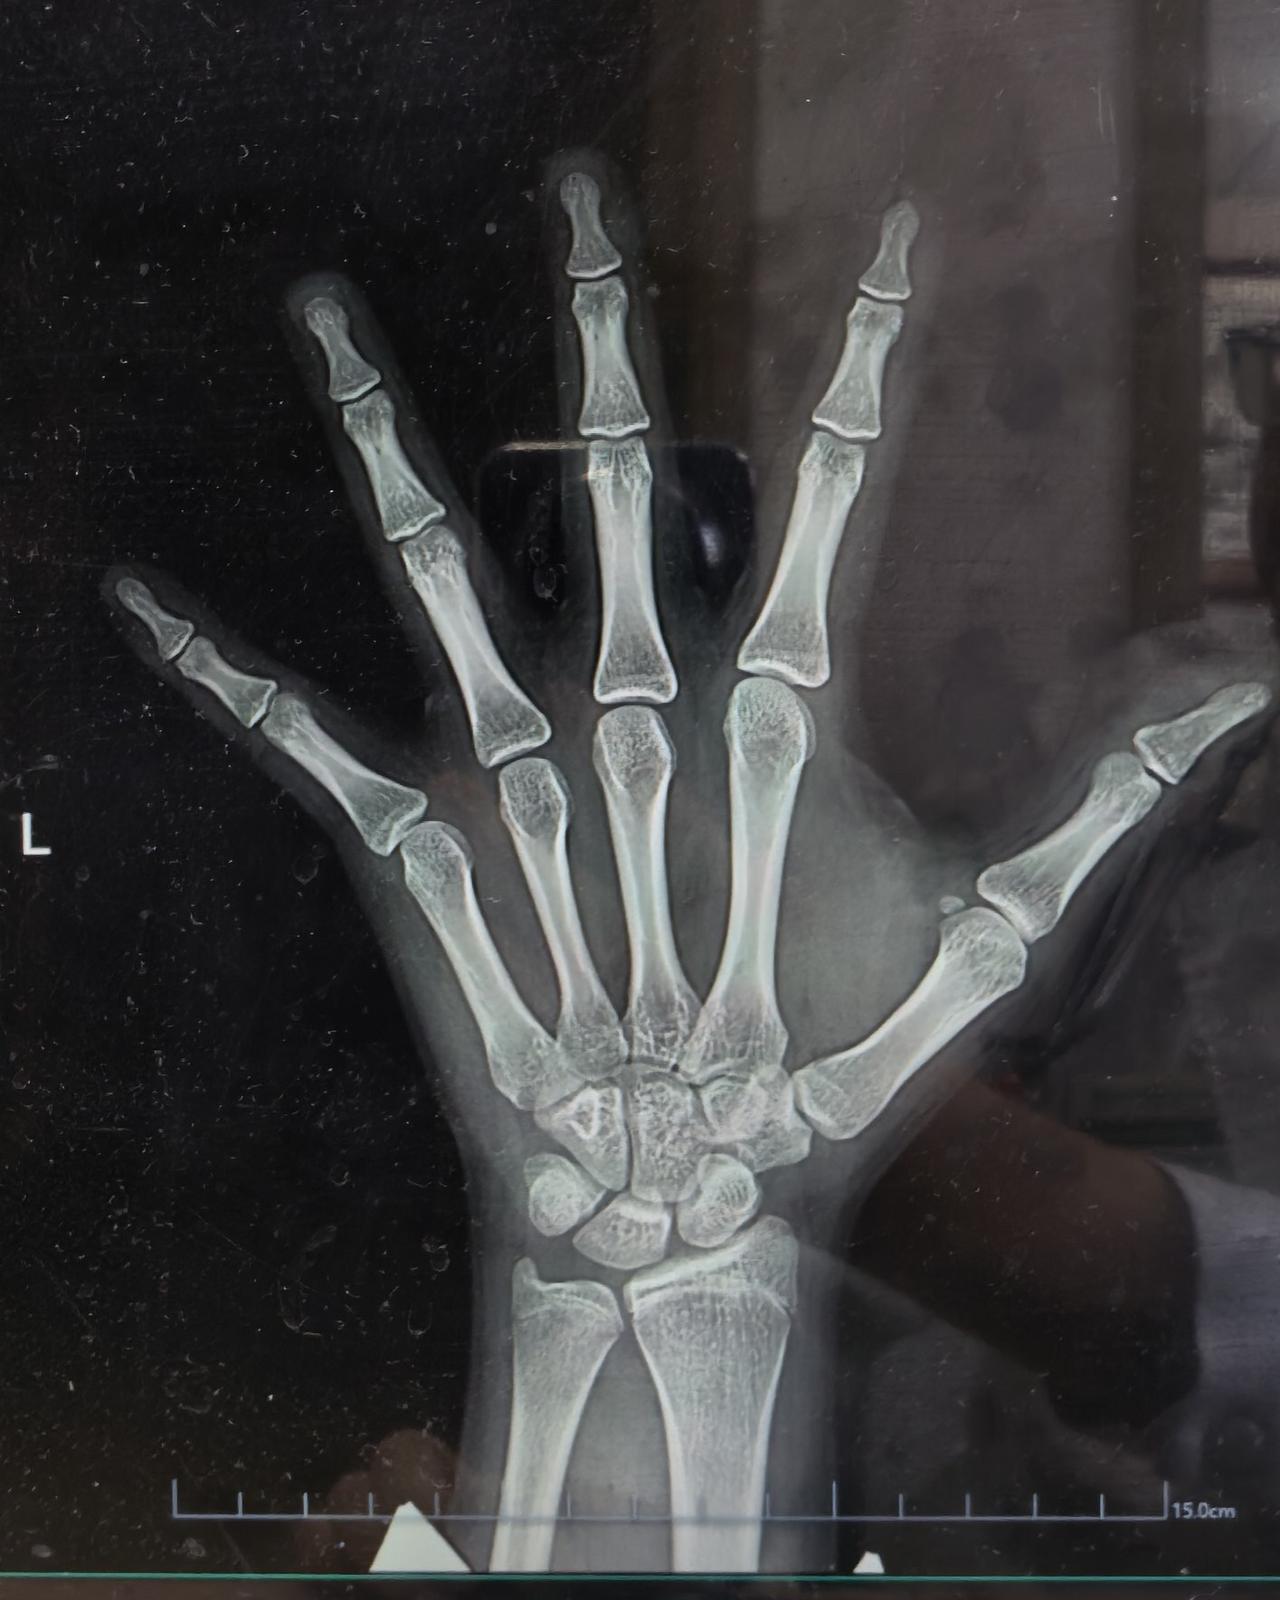

男孩12岁4个月,身高143厘米,没有青春期发育迹象,因为身高远低于同龄人,家长

9岁娃身高才124cm,骨龄竟只有7岁?生长监测才是身高密码🔍

最近接诊了一位

9岁娃身高才124cm,骨龄竟只有7岁?生长监测才是身高密码🔍 最近接诊了一位